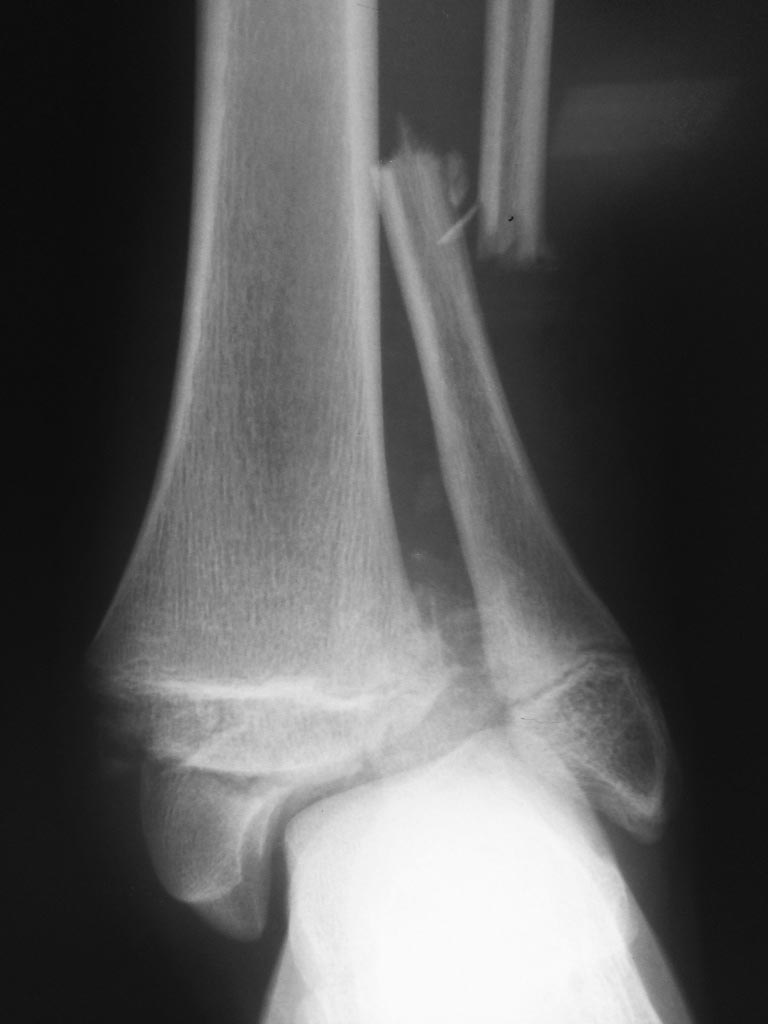

Если позволяет кожа надо сделать открытую репозицию и фиксацию cannulated screws параллелно зоне роста. Это внутрисуставной перелом, репозиция должна быть анатомическая. На фибулу 1/3 tubular plate and syndesmotic screw. В отношение зоны роста время для операции не самое лучшее, но в данной ситуации важнее сохранить сустав. Если будет growth arrest и деформиция эту проблему можно потом решить.

Михаил, несколько с опозданием прочитал Вашу тему. Из предложенных Вами вариантов самым подходящим выглядит третий. С момента госпитализации прошло уже 10 дней. Мягкие ткани уже должны были зажить. Что-нибудь сделали? Согласен с коллегами из Израиля: малоберцовую 1\3 трубкой, суствной блок винтами, межберцовый винт - возможно, но не факт.

Конечно первым этапом можно было бы зафиксировать малоберцовую, это значительно бы улучшило ситуацию с суcтавным блоком tibia. После этого cделать КТ и планировать реконструкцию сустава с фиксацией винтами. ... В 15 лет считайте день за полтора у взрослого.

Этот перелом должен быть фиксирован винтами в тибии (TILLOUX FRAGMENT) и синдезмоз и платой фибулы открыто тогда когда мягкие ткани етого позволят.

Пока вытяжение или EX FIX.

Такой перелом можно можно полечить без больших разрезов. На дистракторе добиться репозиции малоберцовой кости и произвести остеосинтез эластичным титановым стержнем, а внутреннюю лодыжку винтами. Судя по снимку ростковая зона б/берцовой кости близка к закрытию и мучиться с параллельным к зоне роста введением винтов не стоит, лучше раньше убрать винты (через 2-3 месяца). Синдесмоз в данном случае не поврежден (у подростков это вообще бывает крайне редко).

Также малоинвазивно фиксировать фрагмент передне-наружного края дистального эпифиза б\берцовой кости. Таким образом получится 3 разреза по 2 см и решится проблема с мягкими тканями.